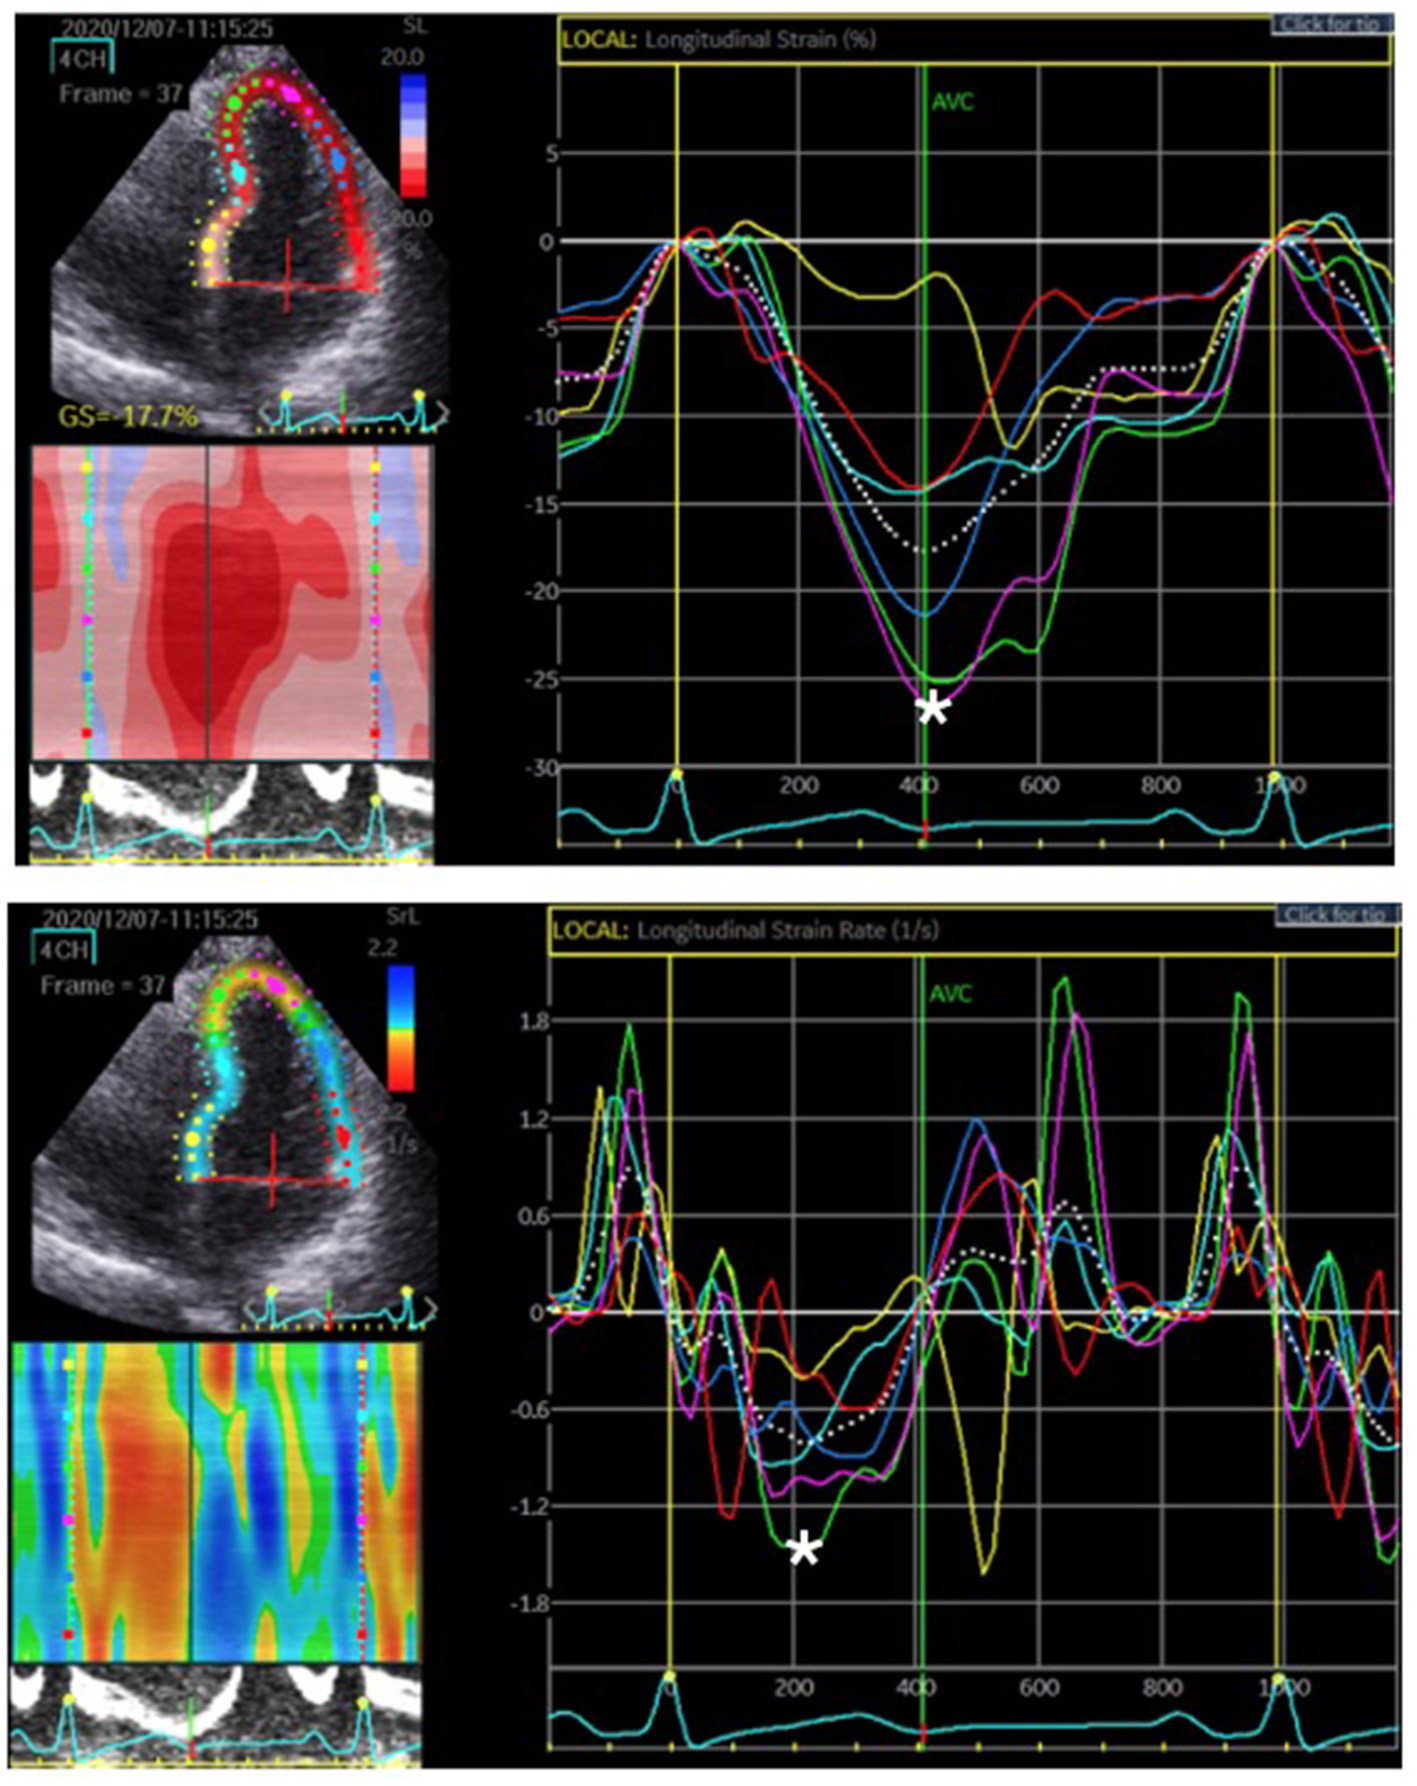

Figure 2

The region of interest, LV myocardium, was tracked. The longitudinal strain and SR were quantified as the peak systolic value in each myocardial segment. The upper figure represents the peak systolic strain. The most negative value, which is denoted by the white asterisk, was measured before aortic valve closure (AVC). The lower figure represents the peak systolic SR. The most negative value is denoted by the white asterisk on the rate/time curve during systole.

2D-STE Analysis

We examined 177 vessels in 59 patients. Among these vessels, seven had hypoplasia. When a vessel had hypoplasia, the myocardium segments supplied by the nearby coronary artery were combined with the adjacent myocardial strain and SR of the adjacent coronary arteries. Therefore, the VMS and VMSR areas were adjusted accordingly. The representative cases of longitudinal strain and SR (Figure 2) with quantification using EchoPac software are presented. The global longitudinal strain (GLS) and SR (GLSR) were initially quantified. However, the GLS and GLSR in the insignificant CAD group were not significantly different from those in the significant CAD group, p = 0.140 and p = 0.294, respectively. The longitudinal strain and SR of the vessel supplied areas in each stenosis severity group showed significant differences between groups, as determined by one-way ANOVA [F(3,169) = 3.53, p = 0.016] and [F(3,169) = 6.86, p < 0.001], respectively (Figure 3). The VMSs and VMSRs in each group were compared. A Tukey's HSD post-hoc test revealed that the longitudinal strain in vessels with very severe stenosis (group IV; n = 29), 13.9 ± 4.3, was significantly smaller than that in vessels with mild stenosis (group I; n = 88), 16.9 ± 4.9, p = 0.023. For the longitudinal SR, vessels with very severe stenosis (group IV; n = 29), 0.9 ± 0.3, and moderate stenosis (group II; n = 37), 1.0 ± 0.2, showed significantly smaller values than that of vessels with mild stenosis (group I; n = 88), 1.2 ± 0.3, p < 0.001 and p = 0.021, respectively (Table 3). The results implied that vessels with more severe stenosis have lower SR values. Furthermore, the results demonstrated that VMSR is superior to VMS as a sensitive predictor of coronary artery condition. The inter-observer variabilities for the measurements of GLS and GLSR were 95.8 and 96.4%, respectively, and those for segmental strain and SR were 97.3 and 95.2%, respectively.